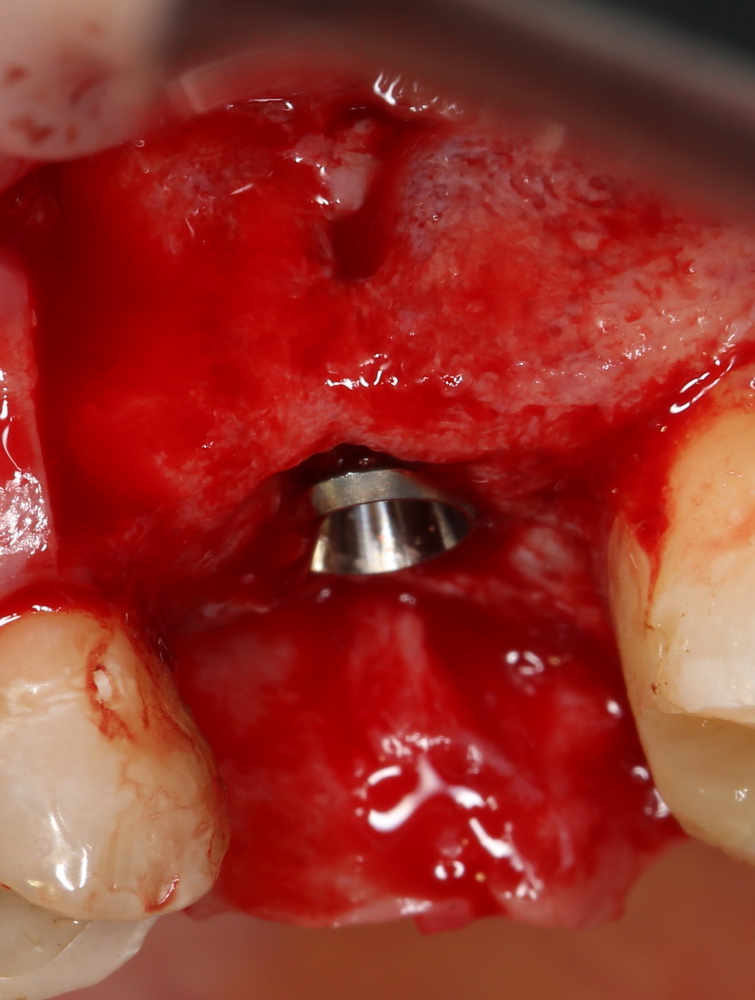

К установке имплантов можно приступать через 3-4 месяца (рис 52, 53):

Рисунок 52, 53. Установка импланта через 3 месяца после удаления зуба и синуслифтинга: слева – скелетирование верхней челюсти, справа – установленный имплантат.